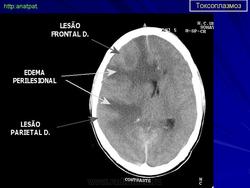

Церебральный токсоплазмоз.

Церебральный токсоплазмоз

Neurotoxoplasmosis

Дифференциальная диагностика изображения